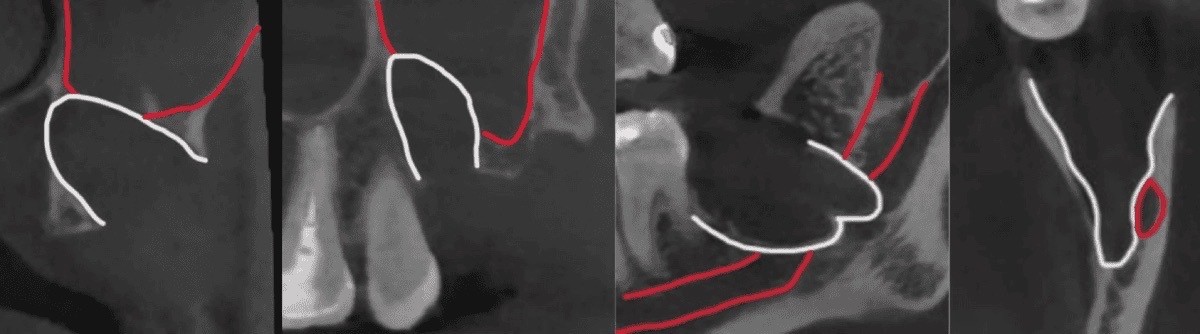

Kompyuter tomografiyasi va 3D rekonstruksiya natijalarida pastki aql tishi sohasida pastki jag‘ nervi ildizlarga juda yaqin joylashgani, yuqori tomonda esa tish yuqori jag‘ bo‘shlig‘i (gaymor bo‘shlig‘i) bilan chegaradosh ekanligi aniqlandi.

Bunday anatomik sharoitda olib tashlashning murakkabligi shundaki, pastki jag‘da operatsiyadan keyin lab va iyak terisining sezuvchanligi pasayishi mumkin, yuqorida esa gaymor bo‘shlig‘i bilan aloqa hosil bo‘lish xavfi mavjud.

• Kattalashtirish nazorati ostida pastki jag‘ nerviga zarar yetkazmasdan va yuqorida gaymor bo‘shlig‘iga tegmasdan aql tishlari ehtiyotkorlik bilan olib tashlandi.

• Operatsiyadan so‘ng nazorat rentgen suratlari orqali tish kataklari anatomiyasi baholandi va ildiz qoldiqlari yo‘qligi tasdiqlandi.